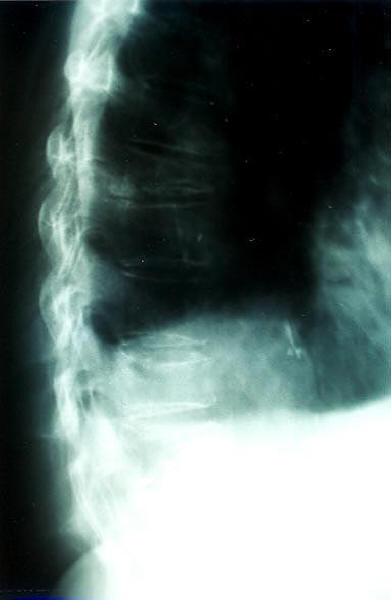

Osteoporosis. Cifosis.

Fractura vertebral, aplastamiento

Acuñamiento vertebral traumático

Aplastamiento vertebral. Gas. Osteoporosis.

Aplastamiento vertebral. Osteoporosis.